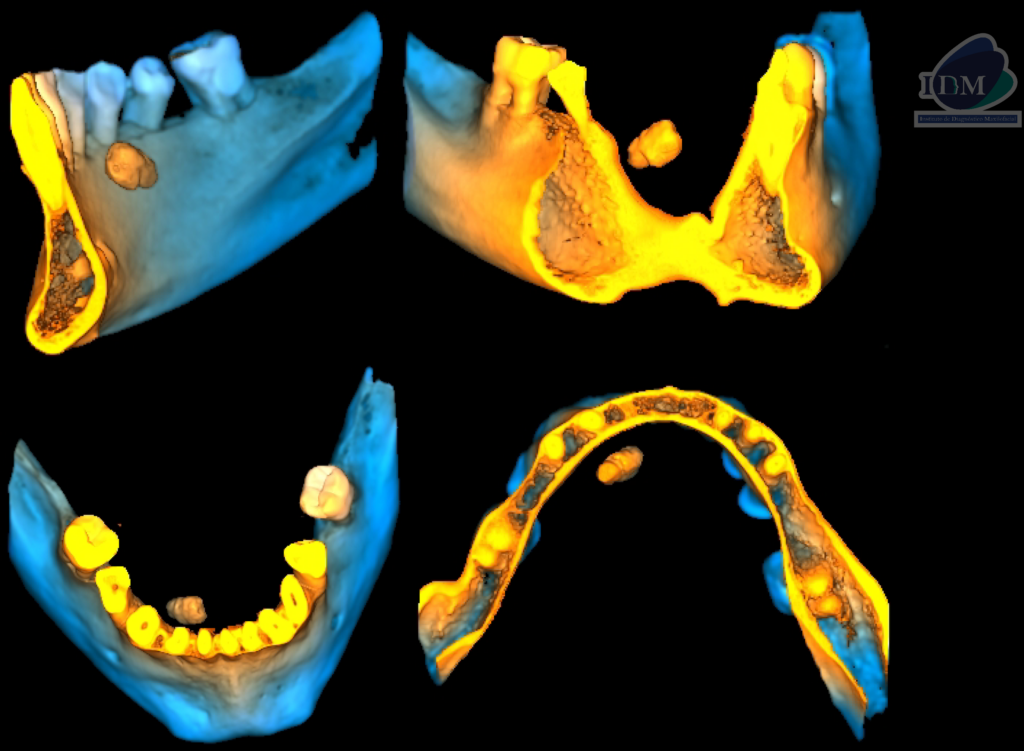

A la evaluación de la tomografía volumétrica (CBCT) en los cortes axiales (Figura 2) y transaxiales (Figura 3), se aprecia imagen hiperdensa de densidad cálcica localizada en lingual del cuerpo mandibular derecho a nivel de tercio apical de piezas 43 y 44, de limites definidos, forma irregular.

CORTES AXIALES